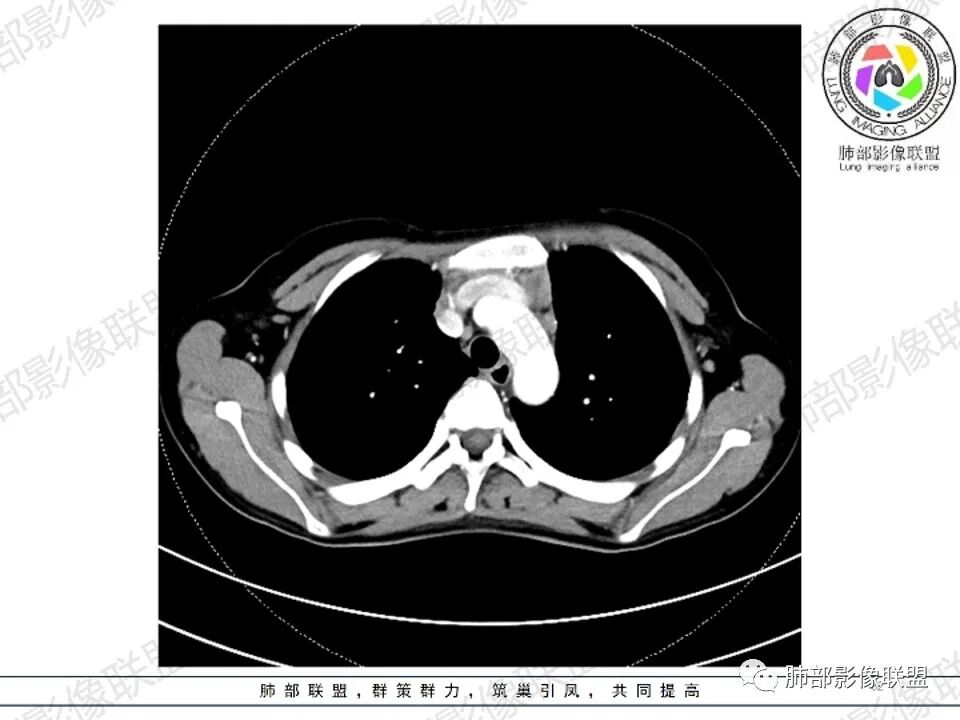

女,27,间断头晕、乏力3年,左眼视物模糊2月。贫血。胸部CT:前纵隔不规则肿块,多结节融合,边界不清,沿主动脉及肺动脉间隙生长,平扫密度欠均匀,增强扫描可见多发低密度坏死,纵隔血管供血穿行,腋窝多发大小不等淋巴结肿大。考虑恶性病变,胸腺癌?肉瘤?淋巴瘤?鉴别胸腺瘤、结节病等。

年轻女性,慢性病史,前纵隔居中肿物,多发肿大淋巴结融合,不均匀强化,坏死边界清,可见血管飘浮征,双侧腋窝淋巴结肿大,定性恶性,年龄及肿物位置,坏死边界可排除胸腺瘤及生殖系统肿瘤,坏死边界清,血管飘浮,腋窝淋巴结肿大,病史较长,均支持淋巴瘤

CT:定位纵膈病变,前中纵隔多发肿块,质软,塑形,密度不均匀,边界清楚。增强不均匀强化,坏死边界清楚,血管漂浮征。双侧腋下多组淋巴结肿大,明显异常强化。

2.影像显示前纵隔不规则块状影,依势贴附心脏大血管旁,密度不均,边界不甚清楚,有结节融合感。

3.病灶轻度不均匀强化,可见血管穿行,散在液性低密度区。

双肺门未见肿大淋巴结。

4.双侧腋窝区见增大淋巴结,边界清楚。